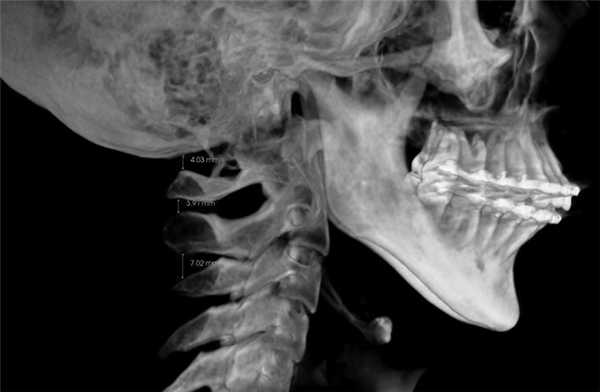

3. Оценка положения шейных позвонков (краниовертебральные функциональные пространства по M. Rocabado). В норме расстояние между C0—CI (затылочная кость и I шейный позвонок) и CI—CII (остистыми отростками I и II шейных позвонков) — 6,5±1—2,5 мм (рис. 8) [14].

4. Краниовертебральное центральное соотношение по M. Rocabado. На КЛКТ также есть возможность анализа ротаций первого и второго шейных позвонков. Измерение проводят от заднего бугорка первого шейного позвонка к зубу второго шейного позвонка, при этом большее расстояние свидетельствует о ротации CI в данную сторону (рис. 9).

Рис. 9. Ротация первого шейного позвонка (CI) вправо, так как расстояние между CI и зубом CII больше с правой стороны — 5,09 мм; слева — 3,43 мм.

Ротации шейных позвонков, уменьшение функциональных пространств служат причиной головных болей напряжения и лицевых болей, поэтому при обнаружении данных патологий необходим комплексный подход в лечении.